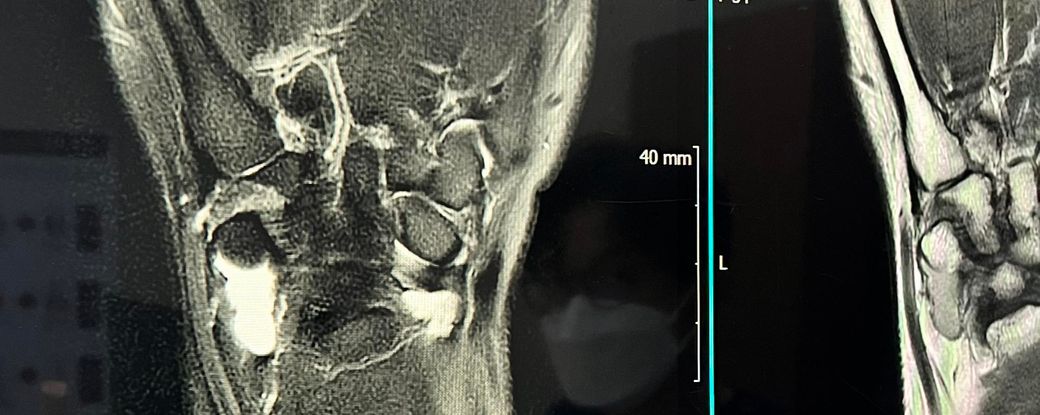

손목 사진인데 정확히 어떤상태인가요?

한의원에서 찍은 사진인데 병원 가기전에

궁금해서 물어봅니다 ㅠ 답변 듣고싶습니다.

손목이 찌릿거리는 느낌이 있긴합니다.

아프기도하구요

사진상으로많은걸확인할수는없는데요 좀더 정확한 확인을위해서는 다양한 사진들이필요할수있습니다

손목에서 찌릿하고 아픈 증상이 있다면 손목 터널 증후군 이나 손목 인대 손상, 건초염 등이 의심됩니다. 한의원 엑스레이는 연부조직 확인이 어려워 정형외과에서 초음파나 mri 등 정밀 검사를 받아보는 것이 정확한 진단에 도움이 됩니다. 증상이 지속된다면 병원 방문을 권장드립니다!

현재 사진 한장으론 정확한 판독을 하긴 힘들며 제한이 있을 수 있습니다.

현재 사진상으론 인대와 힘줄 사이에 염증 또는 부종이 보여지지만 정확한 판단을 하기엔 어렵기에 한의원에서 촬영 당시 판독 소견 또는 병원에 내원하셔서 한번 더 판독 소견을 들어보시길 바랍니다.

보통 진단은 검사 + 진찰을 통해 명확한 진단이 가능하기에 지금으로썬 골절이 아니라면 연부조직(인대, 힘줄, 연골, 근육 등)의 손상으로 인한 통증으로 보여집니다.

대표적으로 손목터널증후근, 건초염, 신경손상(찌릿한 느낌), 낭종 등을 의심해볼수있습니다.